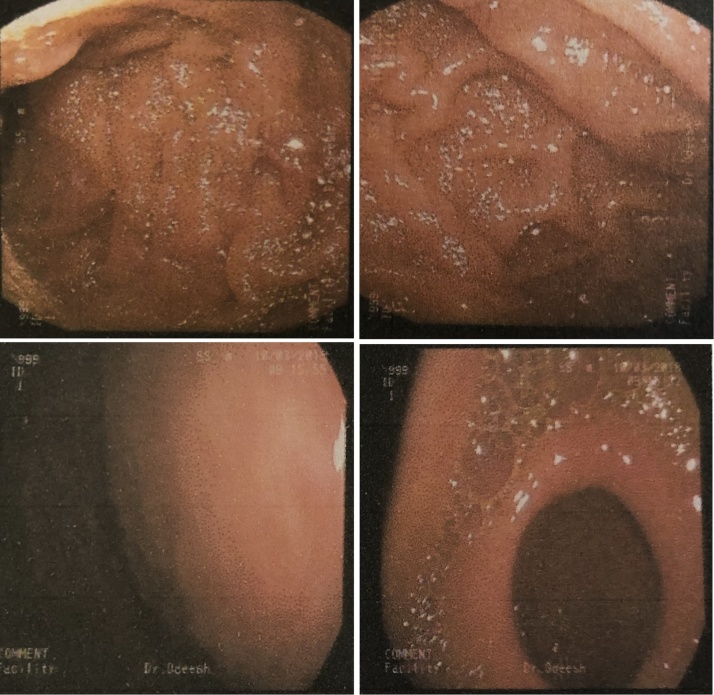

Gastroscopy showed a soft tissue mass with an intact mucosa in the anterior gastric wall, biopsies were taken which revealed fatty tissue with no evidence of malignancy (Fig. 2).

Fig. 2.

An endoscopic view of the stomach showing a soft tissue mass causing bulging of the gastric wall with intact mucosa over it.